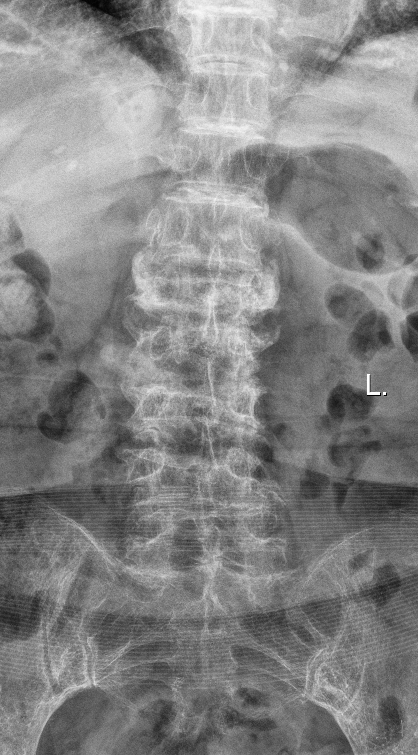

胸腰椎MRI检查结果显示:腰1椎体新近压缩性骨折伴积气,继发椎管狭窄;腰2、3椎体及腰4椎体上缘新近骨折。

影像学结果明确了患者为“骨质疏松伴多节段病理性骨折”,并伴有明显的脊柱后凸畸形和腰椎不稳。骨密度检测T值-4.25,提示重度骨质疏松。

影像学检查提示多节段脊柱病变

接诊后,科室为吴婆婆安排了详细的影像学检查,结果令人震惊。磁共振显示,她的骨折远非此前所知的一处,骨折下方的三节椎体腰2至腰4多个椎体都出现了新鲜压缩性骨折。更关键的是,最初的腰1椎体骨折并未愈合,属于“骨折不愈合”状态,并在重力作用下逐渐塌陷,导致脊柱后凸畸形(俗称“驼背”)。